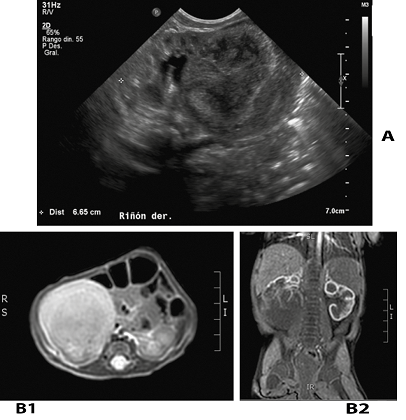

Ecografía abdominal: Riñón derecho aumentado de tamaño con una masa sólida, voluminosa, de 4,4 x 4,3 x 4,8 cm, heterogénea y vascularizada al Doppler, ubicada en polo inferior, sin compresión vascular ni dilatación de la vía urinaria ( Figura 2A).

Tomografía computada de abdomen con contraste: Voluminosa formación nodular de 5,0 x 4,1 x 5,1 cm, heterogénea, en polo inferior del riñón derecho, de aspecto atípico primario. Excreción urinaria conservada en polo superior ( Figura 2B).